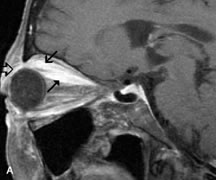

INTRAOCULAR TUMORS

On MRI, uveal melanomas have a typical appearance that helps to differentiate them from other primary and secondary intraocular tumors as well as choroidal detachments. Pigmented melanomas are hyperintense on Tl-weighted images, hypointense on T2-weighted studies, and hyperintense on proton density–weighted examinations (Fig. 24).30,31,50,80–82 These signal characteristics have been attributed to the paramagnetic properties of melanin because of stable free radicals that shorten the T1 and T2 relaxation times. Moderate enhancement is seen on postgadolinium T2-weighted images. Gadolinium-enhanced T1-weighted images are particularly sensitive in detecting choroidal melanomas.83 MRI may be less sensitive in detecting extrascleral extension of tumor than echography performed by an experienced ultrasonographer.84

Fig. 24. A. T1- and (B) T2-weighted MR scans demonstrate a small nodular intraocular mass (arrows) that is very hyperintense on the T1-weighted scan and hypointense on the T2-weighted image. This signal intensity pattern is due to the presence of free radicals within melanin granules. C and D. Postcontrast fat-suppressed T1-weighted scans demonstrate homogeneous intense enhancement of the lesion and no evidence of seleral penetration or optic nerve invasion.